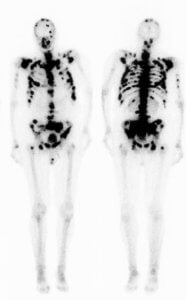

Остеосцинтиграфия, множественные метастазы рака предстательной железы

Целью исследования является выявление зон нарушения метаболизма костей. На самом изображении четко вырисовывается скелет, где можно увидеть более темные «горячие точки», в которых скопились молекулы-индикаторы, что указывает на патологию. Размер и местоположение этих скоплений в костной ткани помогает врачу определиться ,например, с локализацией метастатического поражения костей. В отличие от этого, более светлые «холодные пятна» свидетельствовать об уменьшении кровотока, что встречается при метастатическом поражении рака предстательной железы.

Хотя сцинтиграфия костей может выявить аномалию, само полученное изображение не является диагностическим (оно не указывает на причину проблемы). Поставить диагноз на основании данных только остеосцинтиграфии невозможно. Для постановки окончательного диагноза она должна быть подкреплена дополнительными лабораторными и инструментальными методами исследованиями.